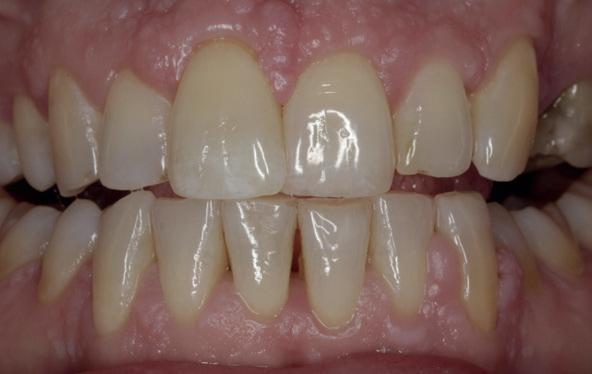

patiënt kon 2 maanden functioneren met de tijdelijke brug, waarna een kort consult werd gepland om te bespreken of hij tevreden was met de esthetiek en functie. Voor de patiënt hoefde niks veranderd te worden (afbeelding 11-14).

Daarna werden de schroefgaten gevuld met Blue M gel, teflon tape en composiet (afbeelding 19 en 20). Patiënt was zich zeer tevreden met het functionele en esthetische eindresultaat (afbeelding 19 en 20). Er was ook een nette hoektand en frontgeleiding. Voor de fonetiek werd een filmpje opgenomen, de F en de S werden netjes uitgesproken (afbeelding 21). De patiënt vervolgt zijn parodontale nazorg bij de mond-

hygiënist waarbij ook de mondhygiëne bij de brug wordt gecontroleerd. Op de OPT na 2 jaar (afbeelding 22) is het botniveau rondom de implantaten stabiel en is patiënt tevreden met zijn vaste brug.